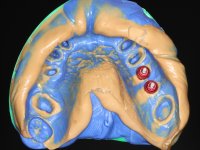

Alginate impressions were made at both arches arcades, accompanied by intermaxillary registration relations and collecting information with facial bow facial bow. In the laboratory, a provisional bridge with 13 elements in autopolymerizable acrylic was built, in which a metallic reinforcement was included. Teeth 1.7 / 1.4 / 1.3 / 2.2 / 2.3 / 2.4 and 2.6 were used as pillars. The metal-ceramic bridge was removed after performing longitudinal cuts with diamond burs. The dental abutments were reprepared and the temporary bridge was relined in the mouth with self-curing acrylic. After confection of the provisional bridge, a gingival epithesis was made using composite resin with gingival tonality in order to function as a mock-up, which allowed the patient to preview the possibility of using gingiva shade ceramics in the final work. This option was approved by the patient. Subsequently, the placement of two implants in the first quadrant was planned and executed. The provisional monoblock was removed for placement of the implants, and after surgery was again cemented provisionally. After the osseointegration period, the impressions were made to the maxilla. In the anterior zone, impregnated gingival retraction cords were used, and in the posterior areas, kaolin paste was used. Implant printing utilized the open tray technique. The printing material used was soft and regular putty addition silicone, both fast-setting. In the laboratory, the model of provisional restorations and the gingiva epithesis mock-up served as orientation for waxing the infrastructure. The plaster work model and the waxing of the infrastructure were placed in a laboratory scanner and yielded a digital work model, in which the scanning of the waxed infrastructure was superimposed. This overlay facilitated the CAD design of the Zr infrastructure. Subsequently, the CAD drawing for a CAM milling process provided the Zr pieces. The infrastructure was pigmented with a pinkish coloration, which favors the subsequent placement of gum shade ceramic. During the modeling of the infrastructure, the need to increase the occlusal wear on tooth 1.4 was detected. This was done in the real working model cast and an acrylic wear control guide was created, which accompanied the proof of the infrastructures. Corrective wear and Zr parts test were performed in mouth. During the test, the color choice of the gum shade ceramic was reassessed. The treatment was finished in the laboratory, and after approval by the patient, was definitively placed in the mouth.